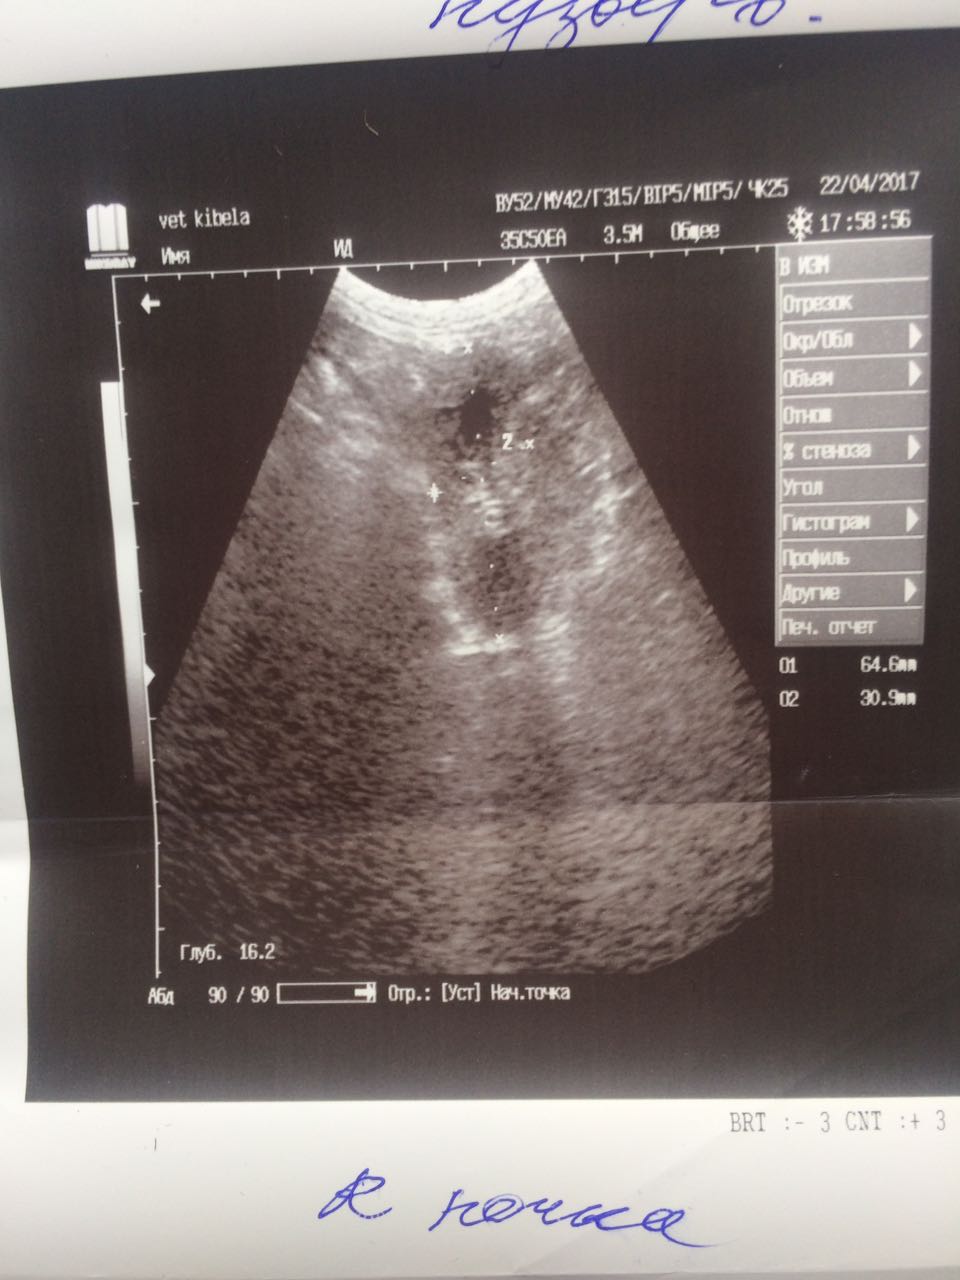

Теперь немного о том что мы нашли на обследование.Не смотря на мои призрачные надежды на доброкачественность образований ,у Лады рак молочной железы. Предположительно похоже на карциному.Конечно хирург сквозь кожу не может разглядеть наверняка ,но полагаясь на опыт может предположить.Из УЗИ мы выяснили ,что пока метастазов в печени,в других органах у нас нет.Есть достаточно большая киста на яичнике и возрастные изменения в почках.